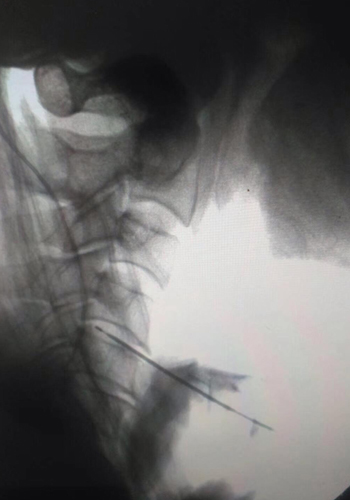

手術前的所有事宜都準備妥當后就開始了第一臺手術,第一臺我們做的是頸4/5、頸5/6椎間盤突出的手術,這場手術大概持續(xù)了40分鐘左右,非常順利,病人一出手術室后就露出了久違的笑容。用胡利民教授的話就是“針已經(jīng)完全正正當當?shù)卮┑轿蚁胍竭_的位置”。當即的手術結束,胡利民教授精湛的技術就受到了馬來西亞學者的高度贊揚。

手術幾乎是一臺接一臺,四臺手術下來,大家都全神貫注地看著顯示屏,尤其在胡利民教授進行穿刺時,大家都拿出了手機拍照,想讓這高難度的操作永刻記憶,便于日后摸索并學習。

直到手術全部做完,馬來西亞的疼痛委員會副會長說:“胡教授,對于前三臺手術,我們覺得是可以的,但是對于第四臺,在我們馬來西亞,一般都建議孔鏡手術治療,且普通醫(yī)生不會也不太敢上手,像你們這激光我們是不會建議的,因為這樣會很難將治療效果達到我們的預期。所以我們覺得您今天跟病人選擇這個方案治療是一個很大膽的想法,這其中緣由和操作可以講講嗎?”胡利民教授聽了一笑說:“不大膽,不大膽,算是保守了,我們是因為考慮到病人的年齡、手術的創(chuàng)傷及恢復,才選擇激光。并且完美的穿刺靶點,是可以解決病人的問題,這樣的創(chuàng)傷還會更小,完整的考慮下來,激光就非不二之選了,所以這其中非??简炨t(yī)生的穿刺技術。”說到這里時,胡主任露出狡黠一笑。馬來西亞學者表示非常的敬佩,并親自去詢問病人的術后感受,聽到病人對整個手術過程的滿意程度,學者們更是欽佩之情溢于言表 。